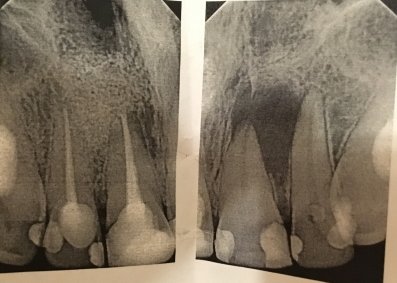

У меня обнаружили 2 кисты на 36 зубе. На одном корне киста маленькая, на втором большая. Снимок прилагается. Врач-терапевт сначала сказал, что нужно удалить кисту, а потом сказал лечить. Просверлил зуб, оставил открытым, сказал полоскать солевым раствором и принимать Кетарол.